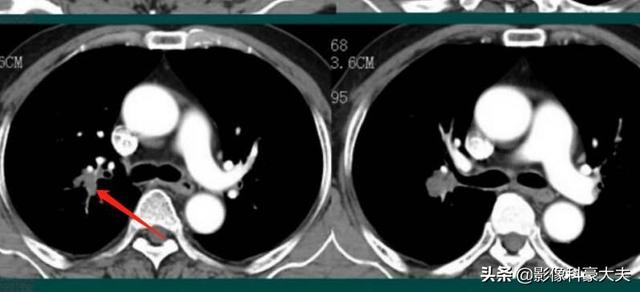

这是一位62岁的老烟民体检,发现左下肺小细胞肺癌,没有远处转移,成功做了切除。小细胞肺癌增长很快,转移早,很难早期发现!这位病人很幸运!